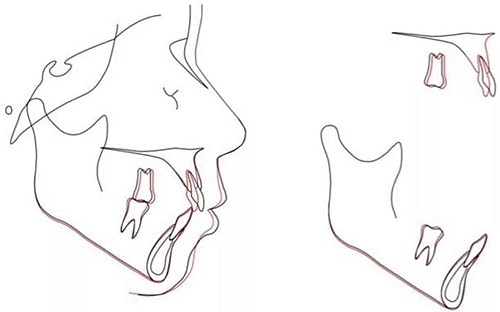

治療后頭側(cè)數(shù)據(jù)提示:無(wú)明顯骨性變化(上頜SNA82.1°,下頜SNB74.9°),上頜前牙得到內(nèi)收,略舌傾,頦部前后位置無(wú)明顯改變,仍未凸面型(圖8,表)。將治療前后圖像重疊后結(jié)果如(圖8及圖9),24月后隨訪結(jié)果見(jiàn)圖10.